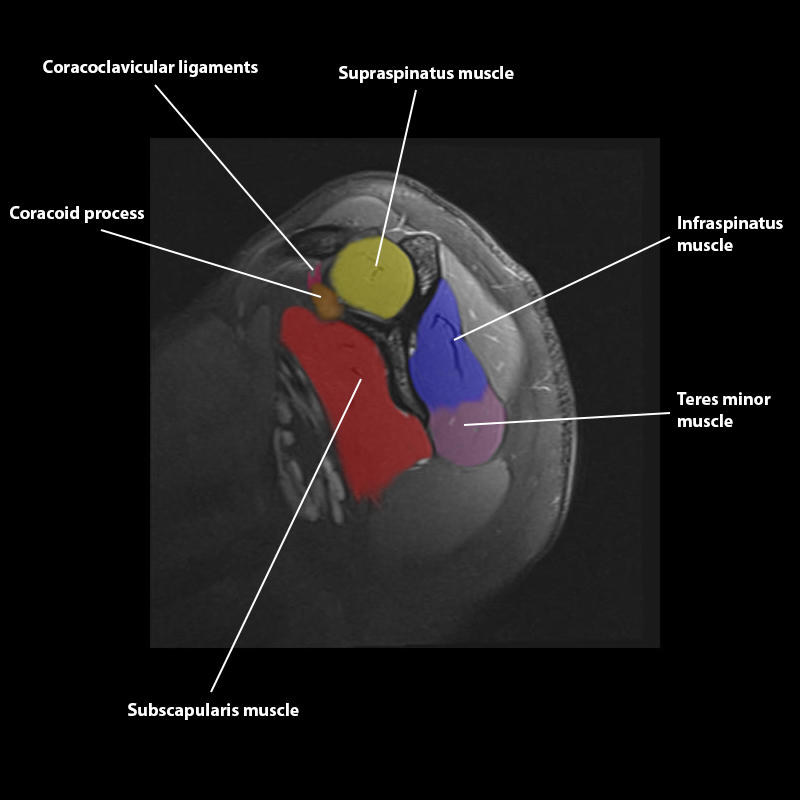

Shoulder MRI Anatomy